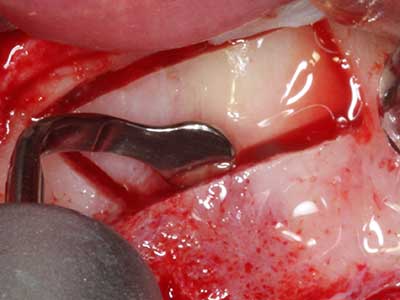

Фиг. 18: Препарация на кортикално покритие с пиезо накрайник за кост (Piezomed, W&H).

Фиг. 19: Хирургичното поле след невролиза и отстраняване на остеотом.

Фиг. 20: Отстраненото костно покритие е поставен отново и фиксиран с винт за остеосинтеза (KLS Martin, Tuttlingen).